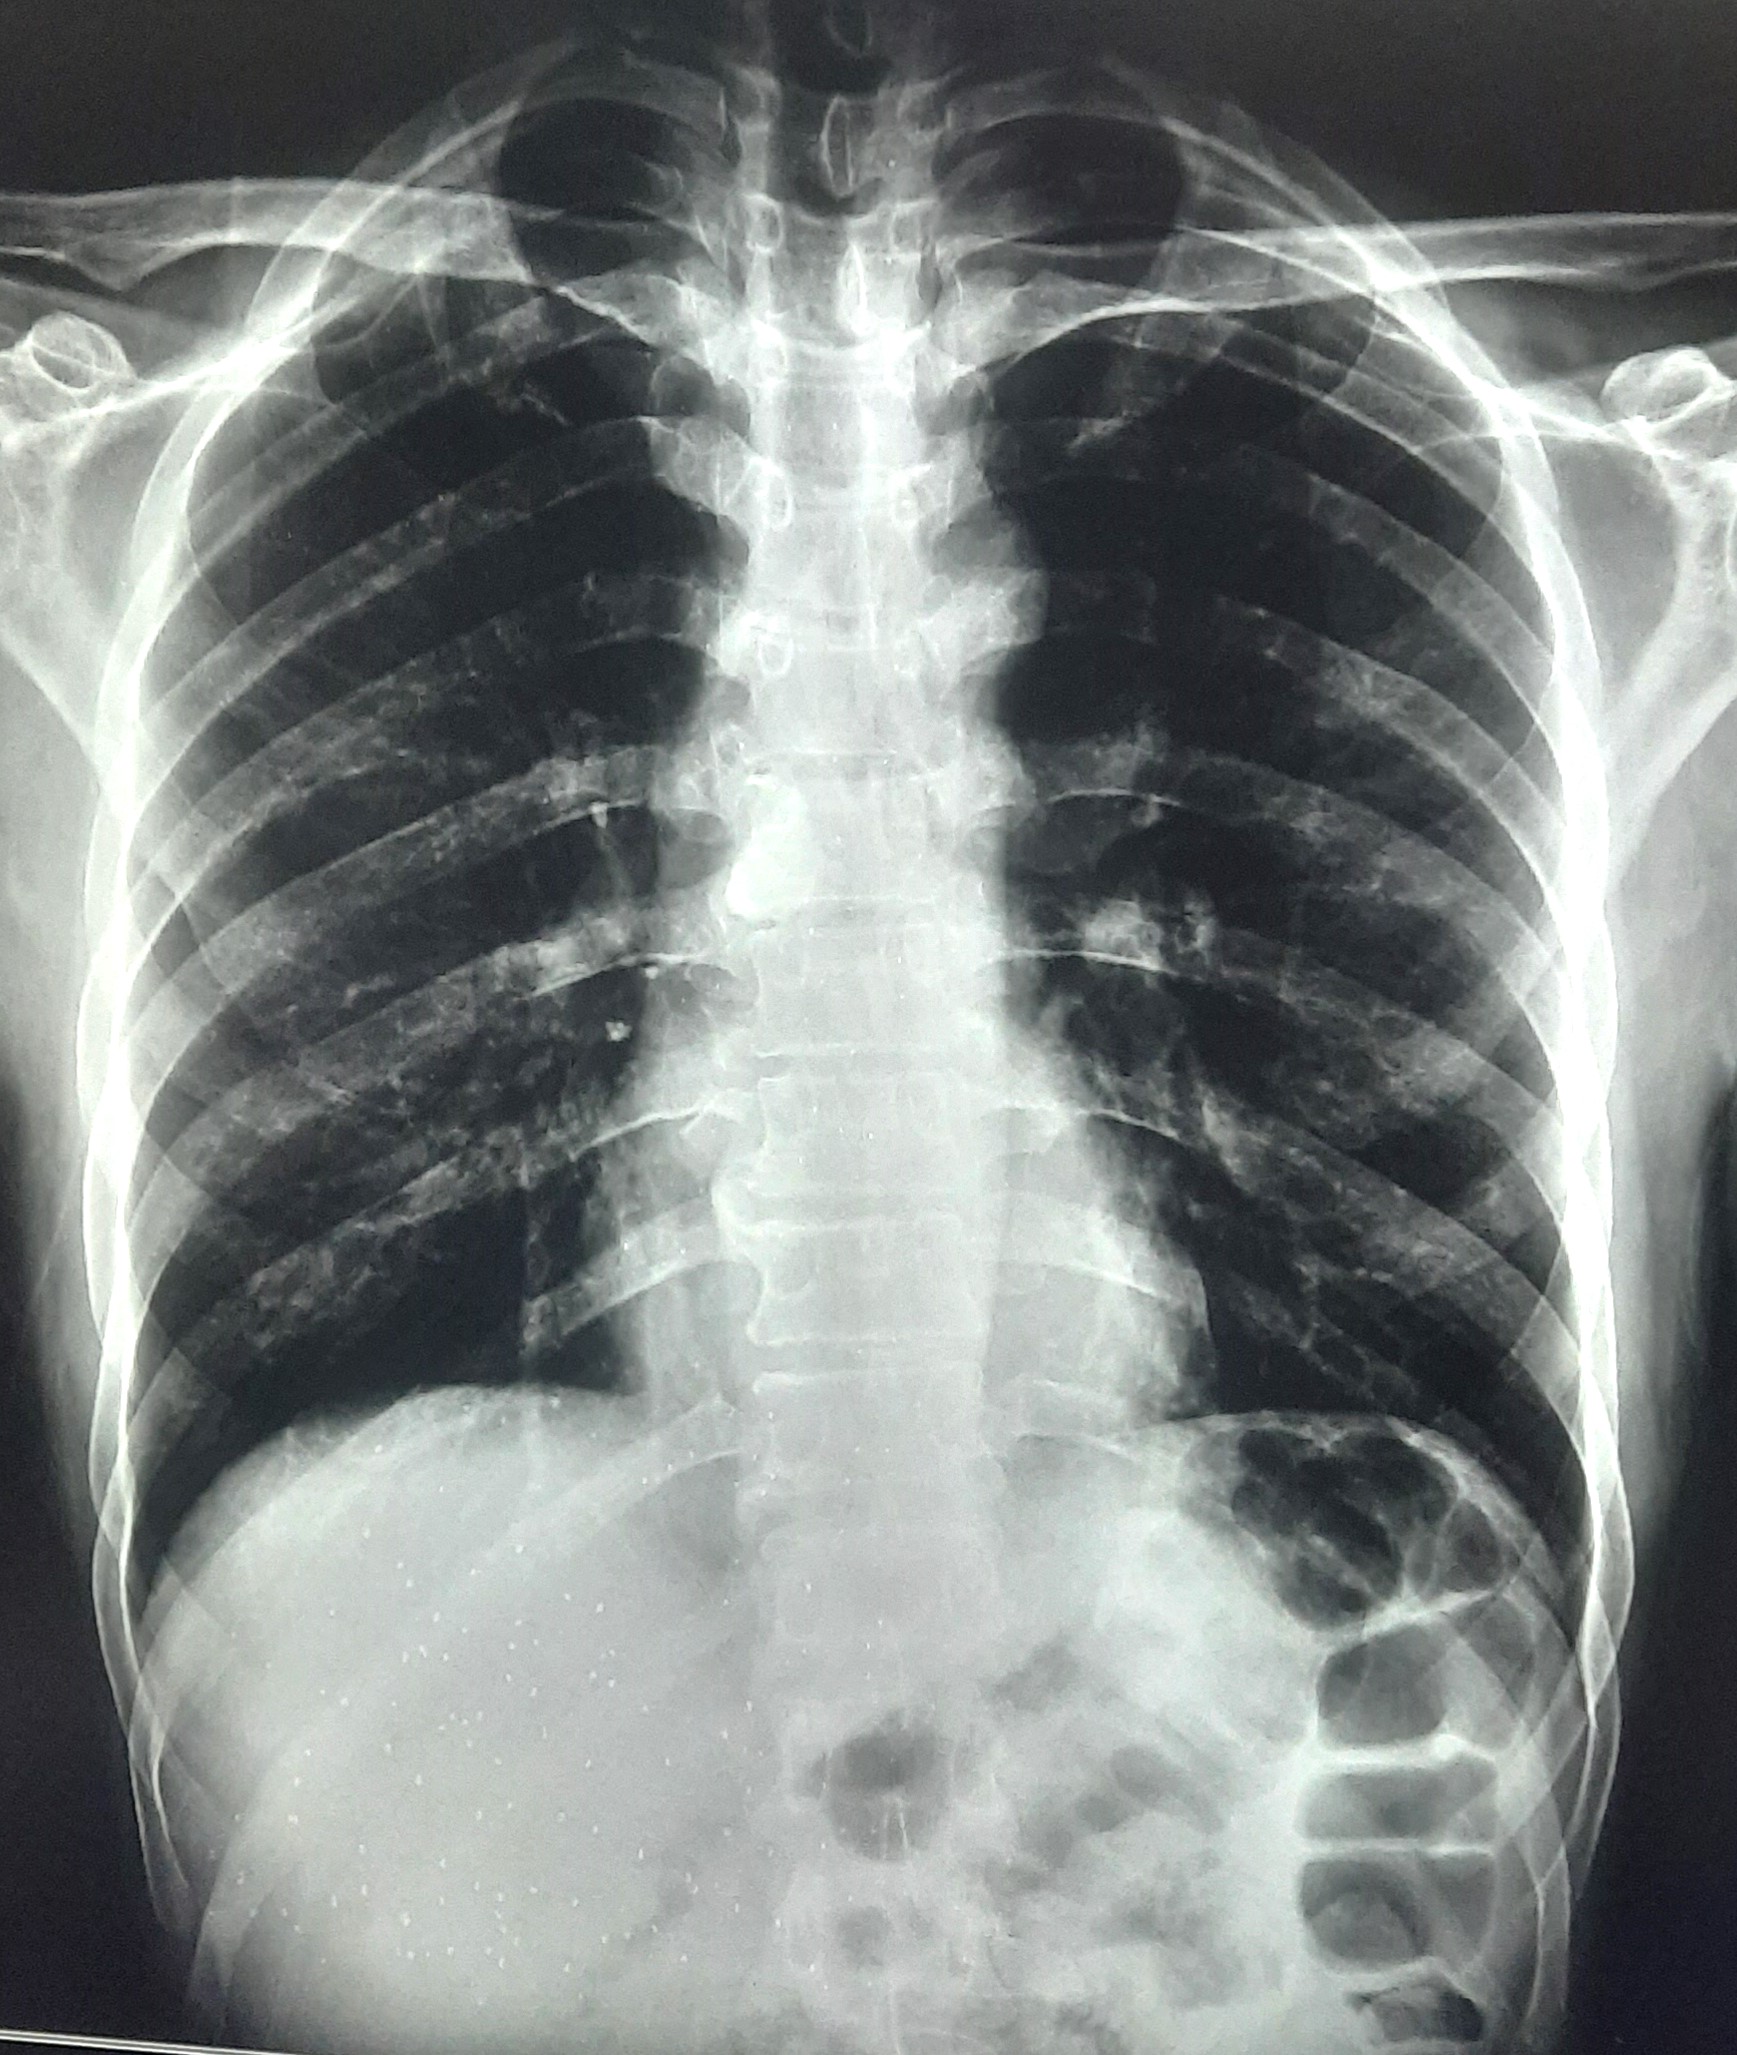

| 251 | IGGMC, Nagpur, Nagpur | P2 | 29-4221 | Ganpat Gaikawad | Consent taken on Paper | 70 Yrs. |

Provisional Diag : post TB sequele?

Final Diag : Fibrosis |

Non-TB Case (Confirmed) | Fibrosis | Abnormality visible on x-ray |